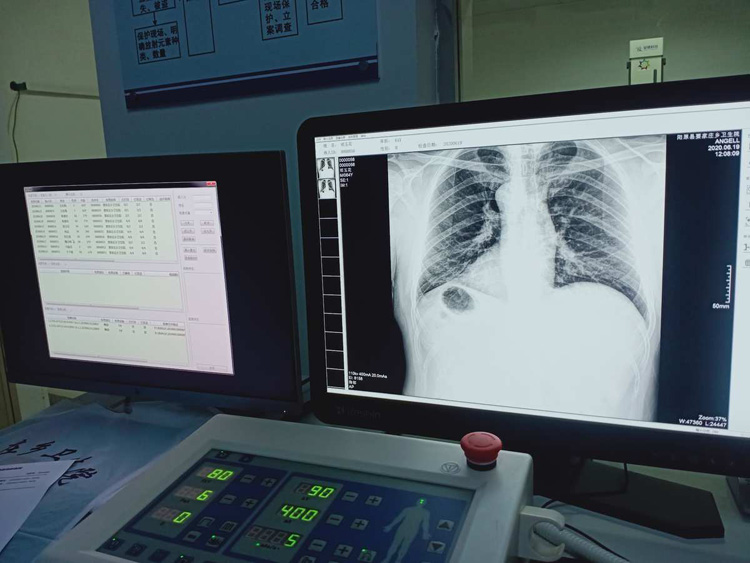

平床DR的平板探测器可以拍摄到高清的数字图像。可以检查身体的某个部位。头部、胸部、腹部、上肢、下肢、正位、侧位、都可以正常的拍摄。很小的剂量就可以采集到高清的检查图像。平板的稳定性也非常的强。DR的平板探测器跟图像结合。噪音低、图像的画质呈现丰富。图像的信息量会跟多提供给医生参考。帮助医生提高诊断的准确性。Digital Radiography就是数字化拍摄。平板探测器特性会对拍摄片的图片质量有关系。

平床DR的数字影像高分辨率,动态范围比较大,密度密度分辨率高可以看到更多细节。拍摄的速度快伪影小。比X光的的灵敏度高很多。辐射小的能量就可以拍到清晰的图像。辐射量少30%以上。特别是对骨头软组织的效果更优。对结节的有没病变的检测查出率更高。